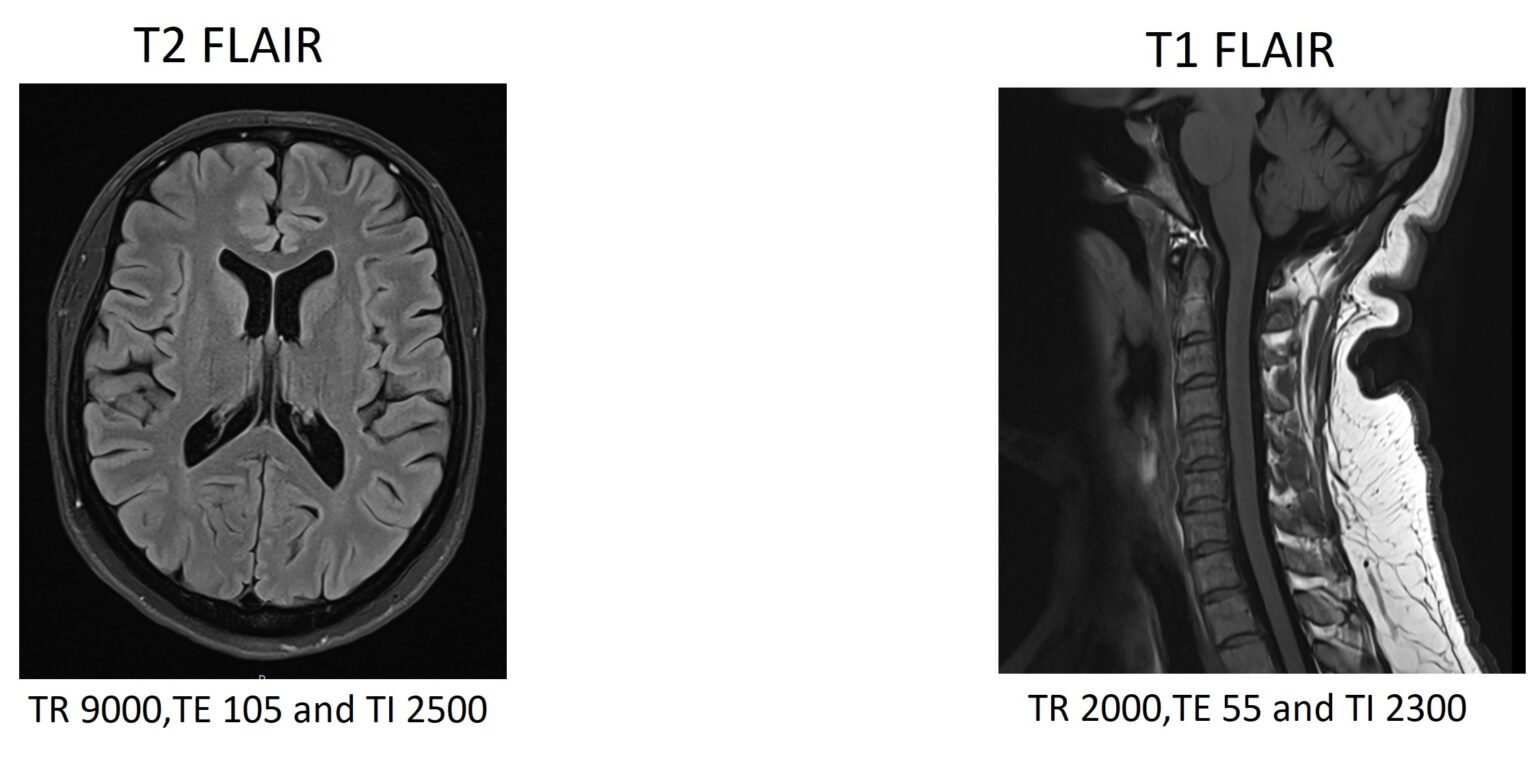

FLAIR MRI FLAIR MRI Sequence Physics, Image and Pathology Appearance Cube Flair Mri This removes signal from the cerebrospinal fluid in the. We aimed to compare the role of 3d cube flair imaging (versus standard 2d flair) in the assessment of white matter. Fluid attenuated inversion recovery (flair) is a special inversion recovery sequence with a long inversion time. Fluid attenuated inversion recovery (flair) is a special inversion recovery sequence with a long. Cube Flair Mri.

FLAIR MRI FLAIR MRI Sequence Physics, Image and Pathology Appearance Cube Flair Mri Fluid attenuated inversion recovery (flair) is a special inversion recovery sequence with a long inversion time. For this purpose we compared cube to a standard 2d flair sequence. We aimed to compare the role of 3d cube flair imaging (versus standard 2d flair) in the assessment of white matter. Fluid attenuated inversion recovery (flair) is a special inversion recovery sequence. Cube Flair Mri.

MRI sequences Inversion Recovery, STIR and FLAIR eMRI Cube Flair Mri We sought to test the cube flair sequence for parenchymal brain imaging in the field of multiple sclerosis at 3 tesla. This removes signal from the cerebrospinal fluid in the. Fluid attenuated inversion recovery (flair) is a special inversion recovery sequence with a long inversion time. This removes signal from the cerebrospinal fluid in the. For this purpose we compared. Cube Flair Mri.

FLAIR MRI FLAIR MRI Sequence Physics, Image and Pathology Appearance Cube Flair Mri This removes signal from the cerebrospinal fluid in the. Fluid attenuated inversion recovery (flair) is a special inversion recovery sequence with a long inversion time. We sought to test the cube flair sequence for parenchymal brain imaging in the field of multiple sclerosis at 3 tesla. For this purpose we compared cube to a standard 2d flair sequence. Fluid attenuated. Cube Flair Mri.

FLAIR vs STIR MRI FLAIR vs STIR MRI image comparison Cube Flair Mri For this purpose we compared cube to a standard 2d flair sequence. This removes signal from the cerebrospinal fluid in the. We aimed to compare the role of 3d cube flair imaging (versus standard 2d flair) in the assessment of white matter. This removes signal from the cerebrospinal fluid in the. We sought to test the cube flair sequence for. Cube Flair Mri.